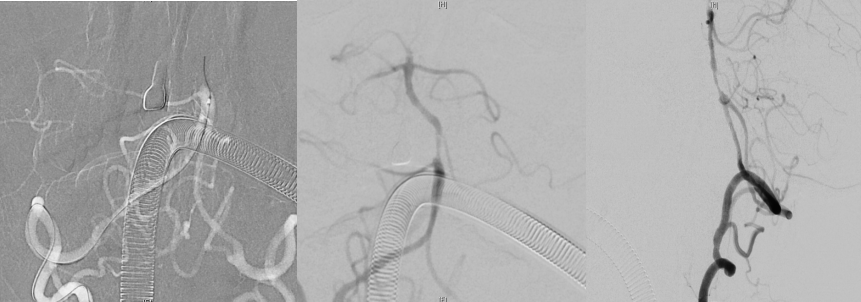

介入手术过程,导丝通过,最终血管成功再通。

最终,患者血管成功再通,且未有任何并发症发生,5天后患者完全康复出院。